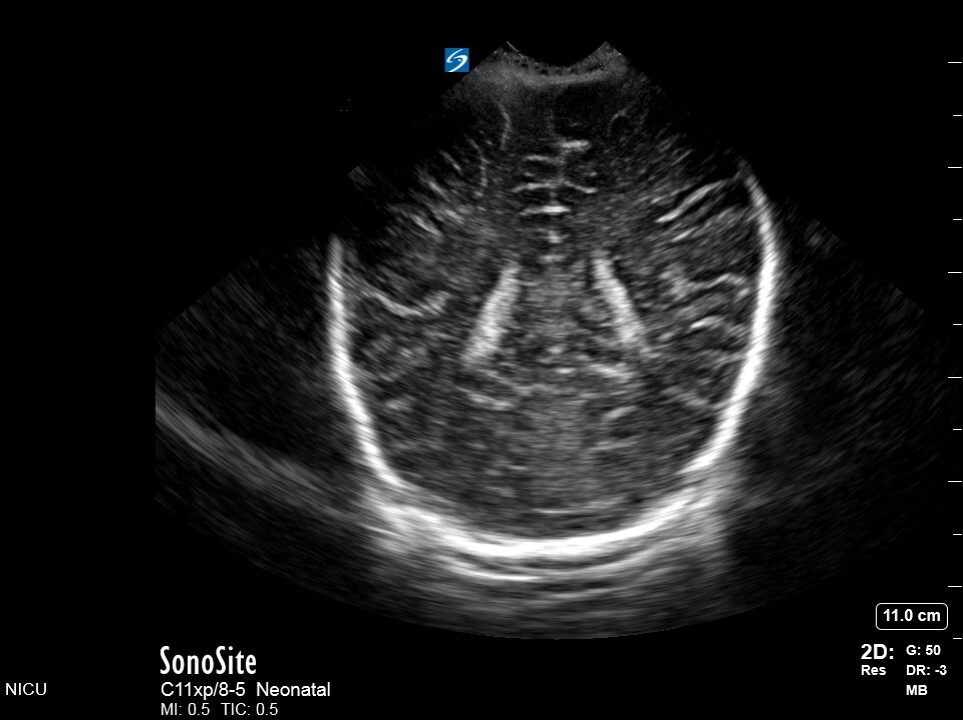

Neonatology C5 1 Image